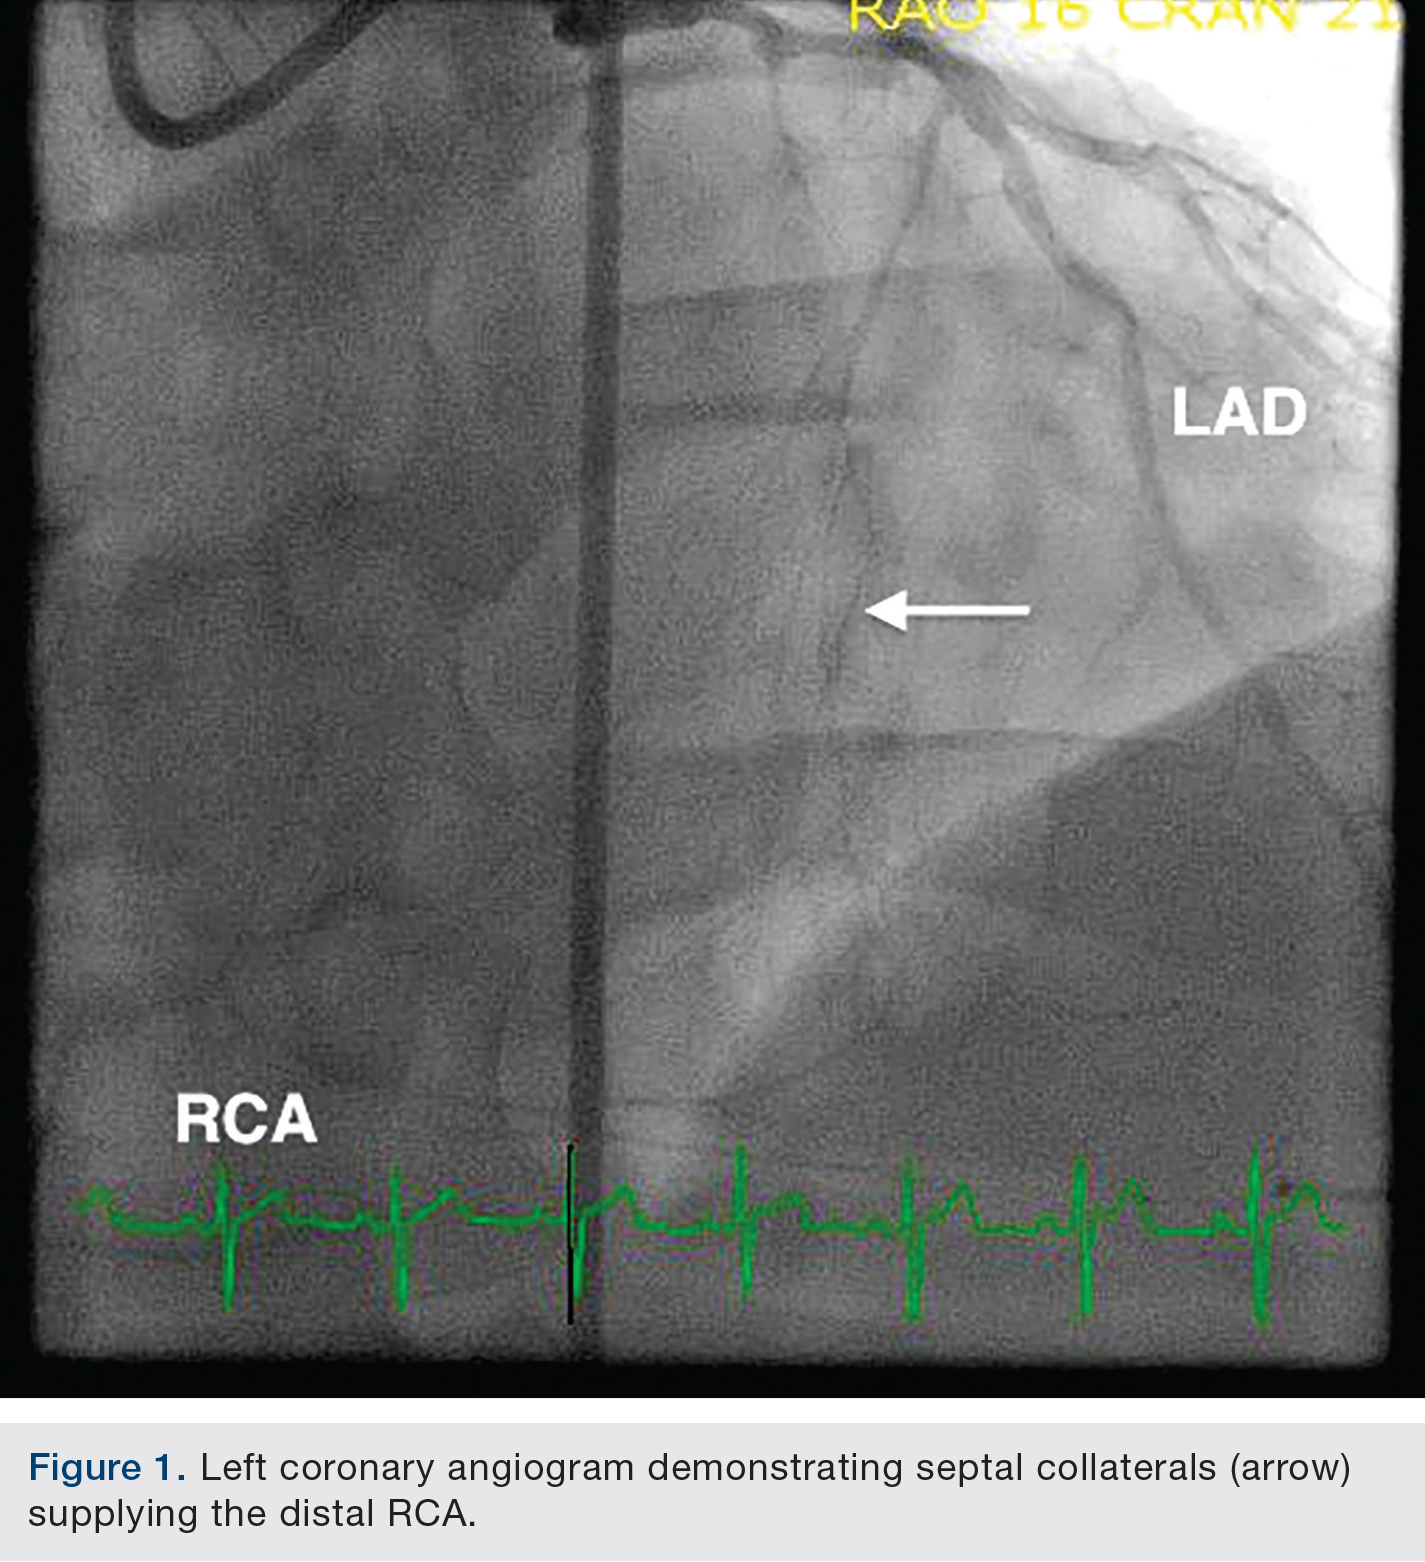

The patient underwent bilateral femoral artery access with 8 French sheath placement. An 8 French Extra Back Up Launcher 4.0 guide catheter (Medtronic) was positioned in the left coronary system and a 7 French Amplatz Left-1(AL-1) (Medtronic) positioned in the RCA ostium. The proximal RCA CTO cap was very ambiguous, with septal collaterals supplying the distal RCA (Figure 1). A retrograde approach via well-developed septal artery perforators was accessed with an Asahi Fielder XT wire (Abbott Vascular) and a 150cm Corsair micro-catheter (Asahi Intecc) (Figure 2).